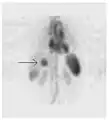

Maximum intensity projection (MIP) of a whole-body positron emission tomography (PET) acquisition of a 79 kg female after intravenous injection of 371 MBq of 18F-FDG (one hour prior measurement).